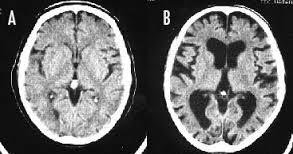

>>322 厚生省が推計して日経が提供した記事を読んで 疑問符だらけなのは理解ができないからだろ? 発達障害者でも目の前に 事実を突きつけられれば認識するぞ それができないんだから もう精神異常者ってことだろ 発達障害で生まれつき脳ミソが異常な上に タバコの吸いすぎで脳ミソが萎縮して (画像B) 完全に認知機能が異常をきたしてんだよ 可哀想にな